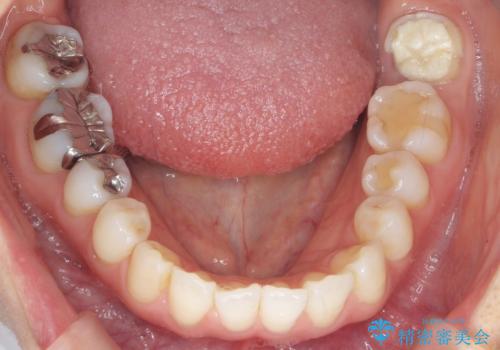

- 昔何回か根管治療した奥歯が膿んでいていて痛みがあることを主訴に来院された患者様です。

精査したところ、左下の奥歯にはひびが入っていて、保存不可能な状態でした。

割れている奥歯を抜去後左上の機能していない親知らずを移植し、生着したのち根管治療・補綴を行いました。